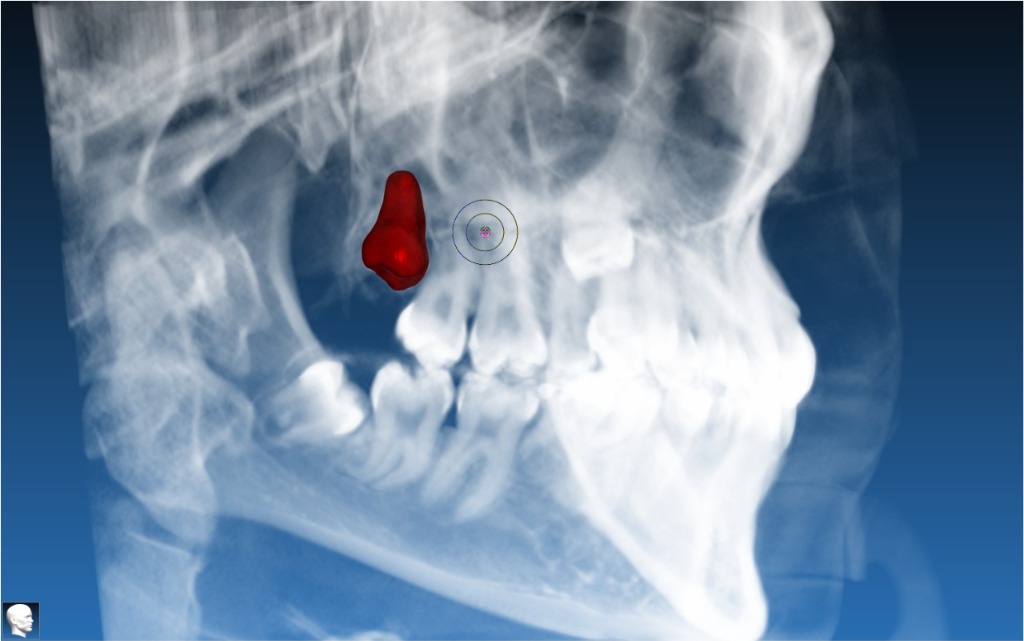

Apical Resection Guide

Targeted osteotomy guide for safe apex localization during apical surgery.

Segmentation Services

CBCT segmentation into clean STL models of nerves, teeth, and bone for diagnostics and surgical planning.